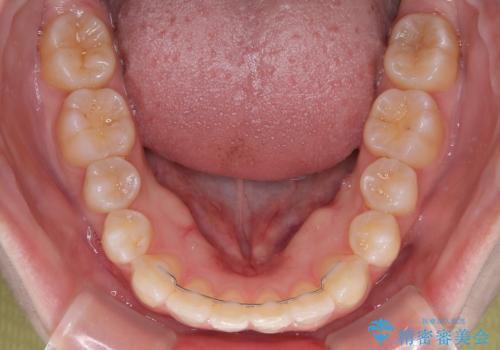

左上の前歯が出ているのが気になる 審美装置による非抜歯ワイヤー矯正

- 左上の前歯が出ていることを主訴として来院された患者様です。

当初はインビザラインを希望されていましたが、職業柄お茶する機会が多く装着時間を確保することが難しいとのことで、相談の上ワイヤー矯正の中では目立ちにくい審美装置で矯正を進めていくこととしました。

1年と少しで矯正治療を終えることができ患者様は大変満足されました。